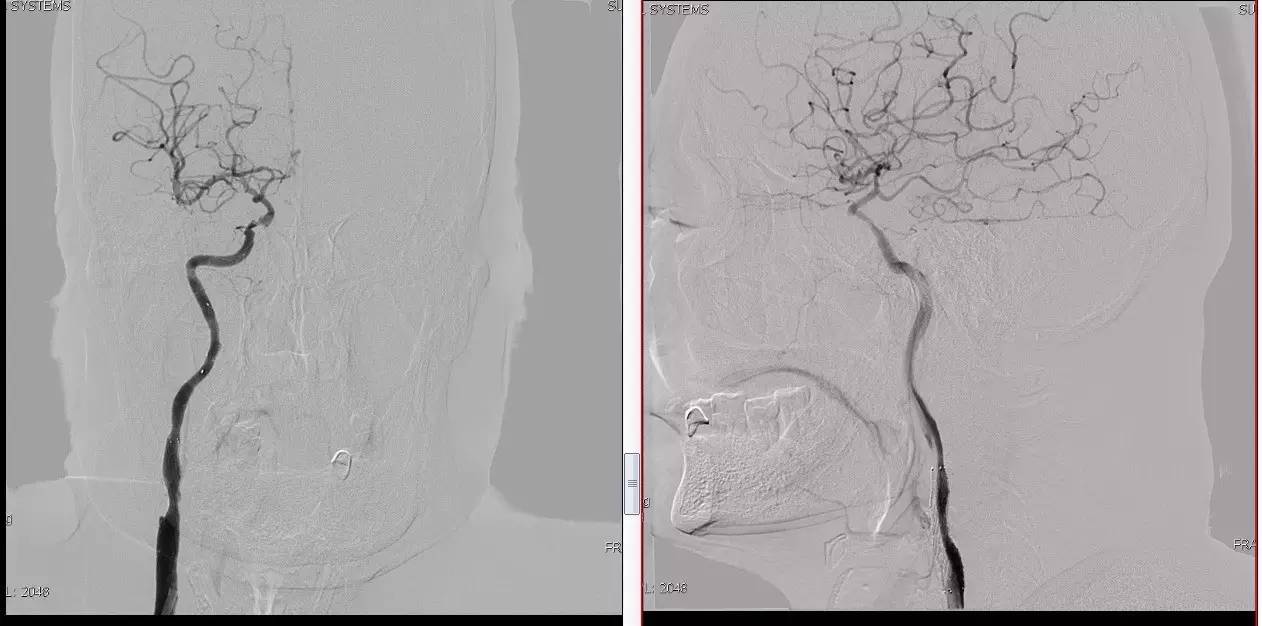

颈动脉次全闭塞 术前评估

》头颅灌注+DSA!

头颅灌注: 关注两侧CBF CBV的对比。

DSA:关注侧支代偿。

》当成颈动脉闭塞开通做,同时8F鞘内套以4F鞘给予微导管足够支撑力。

》避免后扩,分次治疗。

》术中脑保护,首选SPIDER。